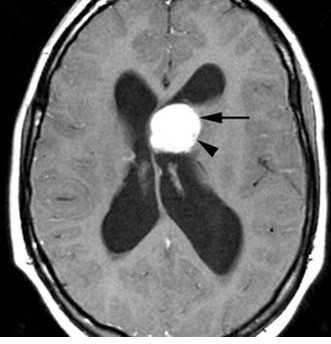

МРТ головного мозга. Туберозный склероз. Гигантоклеточная внутрижелудочковая астроцитома (стрелки). Прорастание в хвостатое ядро. Окклюзия отверстия Монро. Т2-зависимая, Т1-зависимая и Т1-зависимая с контрастированием аксиальные МРТ.

(а) МРТ, Т1-ВИ, аксиальный срез: у мальчика 13 лет с ТС по ходу переднего рога правого бокового желудочка определяются 2 СЭУ.

Кроме того, в переднем роге левого бокового желудочка, прилегая к отверстию Монро, визуализируется двудольчатое объемное образование со смешанной интенсивностью сигнала.

Обратите внимание на кортикальные туберсы, нечеткость границ между серым и белым веществом.

(б) MPT, Т1 -ВИ, более краниальный аксиальный срез: у того же пациента определяются другие СЭУ.

(а) МРТ, Т2-ВИ, аксиальный срез: у того же пациента в левом переднем роге определяется образование дольчатой структуры гиперинтенсивного по отношению как к белому, так и к серому веществу сигнала.

В структуре субкортикального белого вещества под кортикальными туберсами наблюдаются несколько зон гиперинтесивного сигнала в форме «языков пламени».

(б) MPT, FLAIR, аксиальный срез: у того же пациента определяется, что образование дольчатой структуры, расположенное в области переднего рога левого бокового желудочка, не обтурирует боковой желудочек.

Зоны гиперинтесивного сигнала в форме «языков пламени» в структуре белого вещества (БВ) под кортикальными туберсами на данной последовательности визуализируются лучше.

(а) МРТ, постконтрастное T1BИ, режим подавления сигнала от жира: у того же пациента определяется контрастирование СЭУ в области переднего рога правого бокового желудочка, а также контрастирование образования дольчатой структуры в области переднего рога левого бокового желудочка.

Зоны гиперинтесивного сигнала в форме «языков пламени» в структуре БВ на данном изображении видны лучше. Визуализируется один радиальный пучок, простирающийся до границы бокового желудочка.

(б) МРТ, постконтрастное Т1-ВИ, сагиттальный срез: у того же пациента образование левого переднего рога с дольчатой структурой напрямую прилежит к отверстию Монро, но не обтурирует его.

Предполагаемая СГКА у данного пациента наблюдается без хирургического вмешательства и остается стабильной уже в течение нескольких лет.